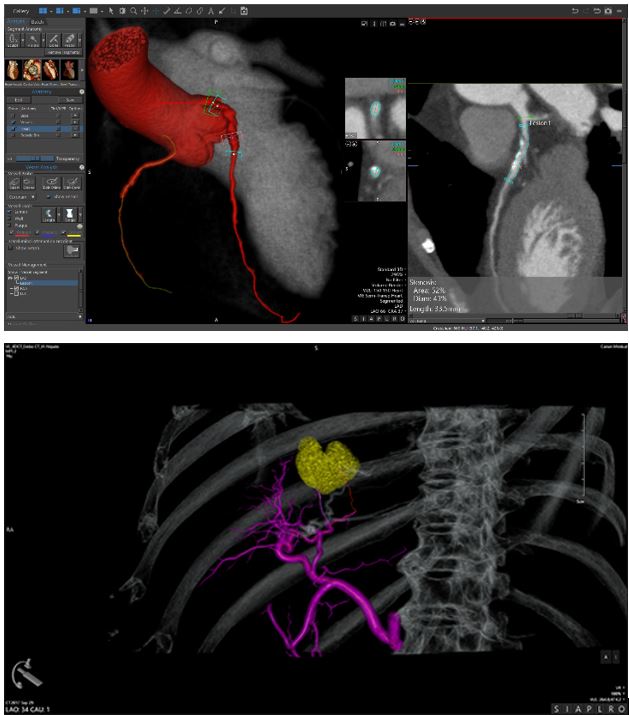

Програмне забезпечення Vitrea дозволяє візуалізувати та аналізувати 2D, 3D та 4D зображення анатомії та фізіологічних функцій за допомогою КТ (комп’ютерної томографії) та МР (магнітного резонансу), ПЕТ, ультразвуку та XR, що дозволяє медичним фахівцям заощадити час та має доступні інструменти для віддаленої роботи у мережі інтернет для ще більшої продуктивності. Програмне забезпечення включає: КТ аналіз печінки, КТ ендоваскулярне планування стента (EVSP), КТ нирки, КТ протікань (endoleak), КТ аорти, КТ сонної артерії та КТ Вілізієвого кола.

Важливі інструменти постобробки включають КТ-аналіз серця, КТ-аналіз мітрального клапана, КТ аорти, аналіз LAA, КТ планування TAVR та КТ планування електрофізіологічних процедур.